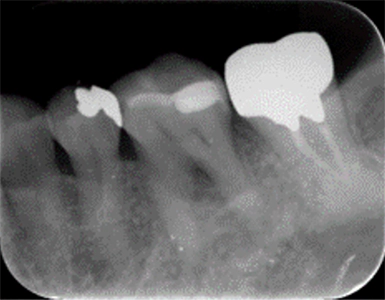

CASE1

歯周組織再生療法(保険診療)

術前

術後(1年後)

年齢・性別 50歳・女性

主訴 市の歯周病健診で歯周病を指摘された

診断名 広汎型慢性歯周炎ステージⅢグレードB

治療内容 歯周基本治療 歯石除去、ブラッシング指導により歯肉の炎症をできる限り改善し、その後歯周ポケットが深く歯槽骨の破壊が大きい部分に対して、歯周外科処置を行った。

治療期間 初診から歯周外科処置まで約5カ月、その後メインテナンス

費用 保険診療にて行う

リスク・副作用 術後の痛み、腫れ、出血が出ることがある

感染の可能性、腫れや再生不良が起こることがある

喫煙や清掃不良、炎症が重度の場合は組織再生の効果が十分得られないことがある

歯肉が引き締まる過程で知覚過敏が起こることがある。